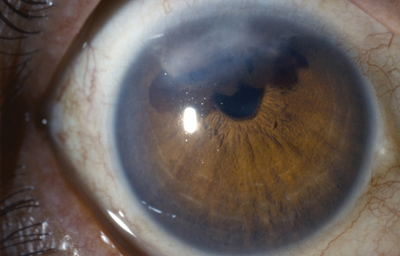

Policória: significa la presencia de varias pupilas en un Iris, es un hallazgo extremadamente raro, aclarando que el término se debe emplear solamente, para los casos en que la apertura esta rodeada por un esfínter completo; si no, es una policoria falsa.

Policoria falsa en midriasis OI: sinequia en el borde pupilar temporal con banda fibrosa 3 a 4; se ve el collarete y el esfínter periféricos a la pequeña pupila, lineas de tracción superiores e inferiores hacia el puente que separa las 2 aperturas de la 1 a las 5 - dentro de apertura pequeña, parece existir un remanente de membrana pupilar.

Archivo Fotográfico Dr. Carmen Barraquer. 1983